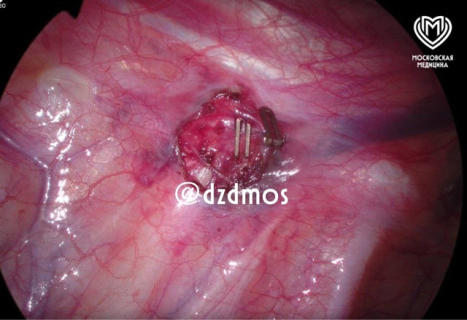

«Избавиться от этой неприятности можно раз и навсегда, сделав операцию. Через два прокола в подмышечных впадинах с обеих сторон клипируются симпатические нервы. После того, как их зажали на определенном уровне, от нервной системы больше не поступает сигнал: «ладони потейте», — рассказал Владимир Гацуцын, детский хирург высшей категории, торакальный хирург хирургического отделения №2, к.м.н.